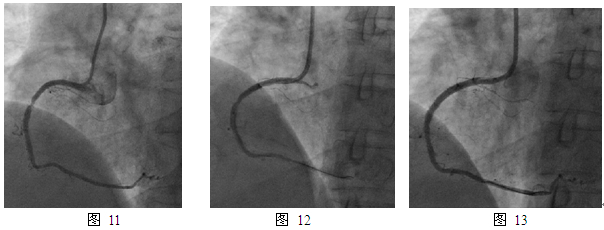

10个月后,患者再次出现活动和安静时胸痛,2013年1月再次住我院。复查冠造,右冠支架内原PEB治疗部位再狭窄80%(图11),再次进行PCI治疗,球囊预扩张后置入Firebird 2支架3.0mm x 18mm,效果满意(图12,13)。术后患者坚持药物治疗,半年临床随访无不适。